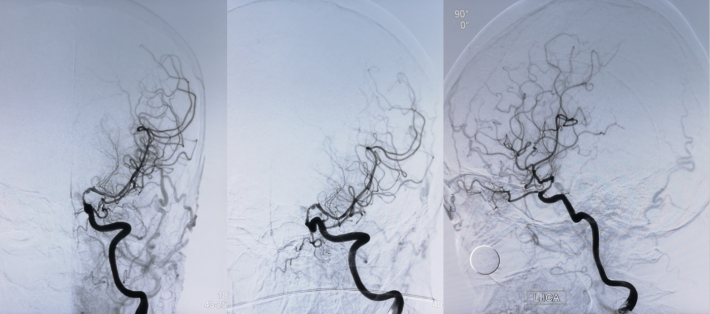

此次入院后,即予行全脑血管造影术,示左侧颈内动脉虹吸段重度狭窄。予患者家属充分沟通后,进一步行左侧颈内动脉虹吸段狭窄球囊扩张+支架植入术。

DSA

考虑狭窄段为夹层样改变,多角度导引导管造影,以更清晰地区分真假腔,选择最佳工作角度

--DSA显示左侧颈内虹吸段狭窄约72%。前交通开放,右侧大脑前动脉通过前交通动脉向左侧大脑前动脉、大脑中动脉供血区有代偿供血。